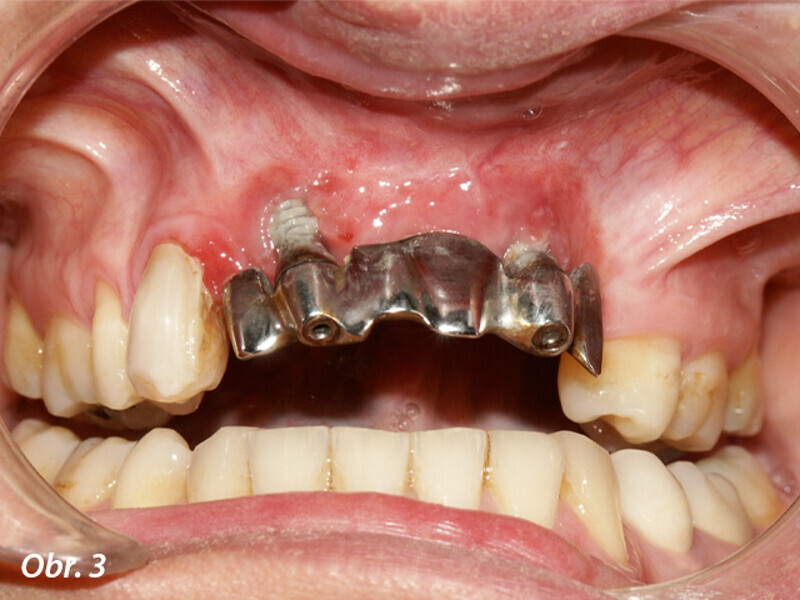

Opětovné implantologické ošetření